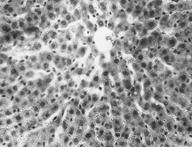

При скармливании крысам мяса цыплят-бройлеров, содержащего свинец, установлено, что структура печени неоднородна (Рис. 5). Наряду с сохранившими нормальное строение дольками, в паренхиме печени обнаруживаются очаги с выраженной зернистой дистрофией, с признаками дистрофического ожирения и участками некроза, наиболее выраженных в дольках с нарушенным балочного строения.

Рисунок 5. Печень. Группа № 2 .

В паренхиме обнаруживаются очаги выраженной зернистой дистрофии с признаками дистрофического ожирения и участками некроза (Увел.400).